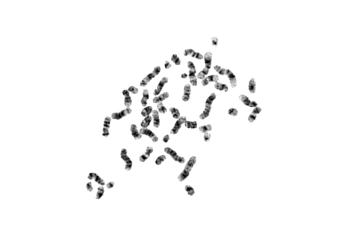

血液肿瘤疾病想要准确的进行诊断需要涉及到一项非常重要的技术:染色体核型分析。

血液病的诊断最初主要依赖于形态学分型,即FAB分型方法,但是随着染色体显带等技术的相继问世,血液病细胞染色体的特异性重排被逐渐发现,血液病的诊断也逐渐发展成形态学、免疫学、细胞遗传学及分子生物学相结合的分型方法,即MICM分型。1999年WHO提出的关于造血系统恶性肿瘤的诊断分型建议中已将染色体和细胞形态学、免疫学及分子生物学一同列为血液病的重要诊断指标。

在多种白血病和其它血液系统疾病中可发现特异性的和非特异性的染色体异常,染色体异常的检出对血液系统疾病的诊断、鉴别诊断等显示越来越重要的作用, 同时在白血病预后判断、指导治疗中起到关键作用。染色体核型分析也同样应用于鉴别白血病微小残留病灶及验证骨髓移植是否成功的常用检测手段。

(慢粒白血病)

染色体核型分析第二代技术(第一代纯手工操作已被淘汰)在全球广泛使用,目前应用于各大医院血液科、检验科、妇产科、生殖中心、计划生育研究所、 职业病防治所以及高校和科研院所等单位。